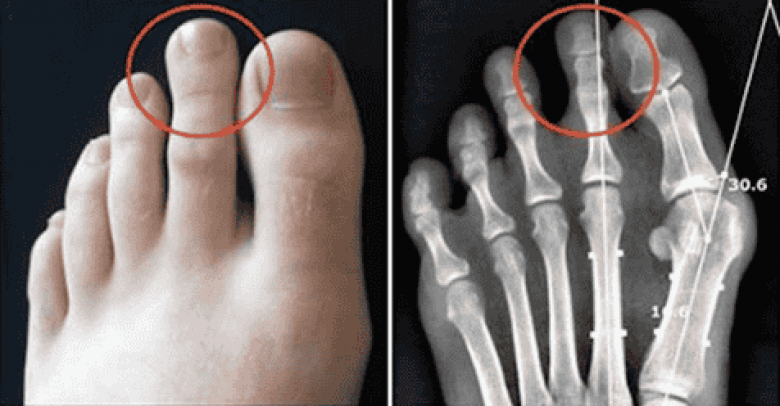

ФОТОВ Индии и Китае долгое время люди учились считывать определенные данные с ног, как бы это странно ни звучало. Некоторые верят, что через ноги можно познать характер человека. Например, если у Вас торчит косточка, значит, Вы часто сталкиваетесь с проблемами. Более того, ум и тело неразрывно связаны, и это может случить признаком отклонений. Давайте посмотрим, что могут сказать ноги о характере!